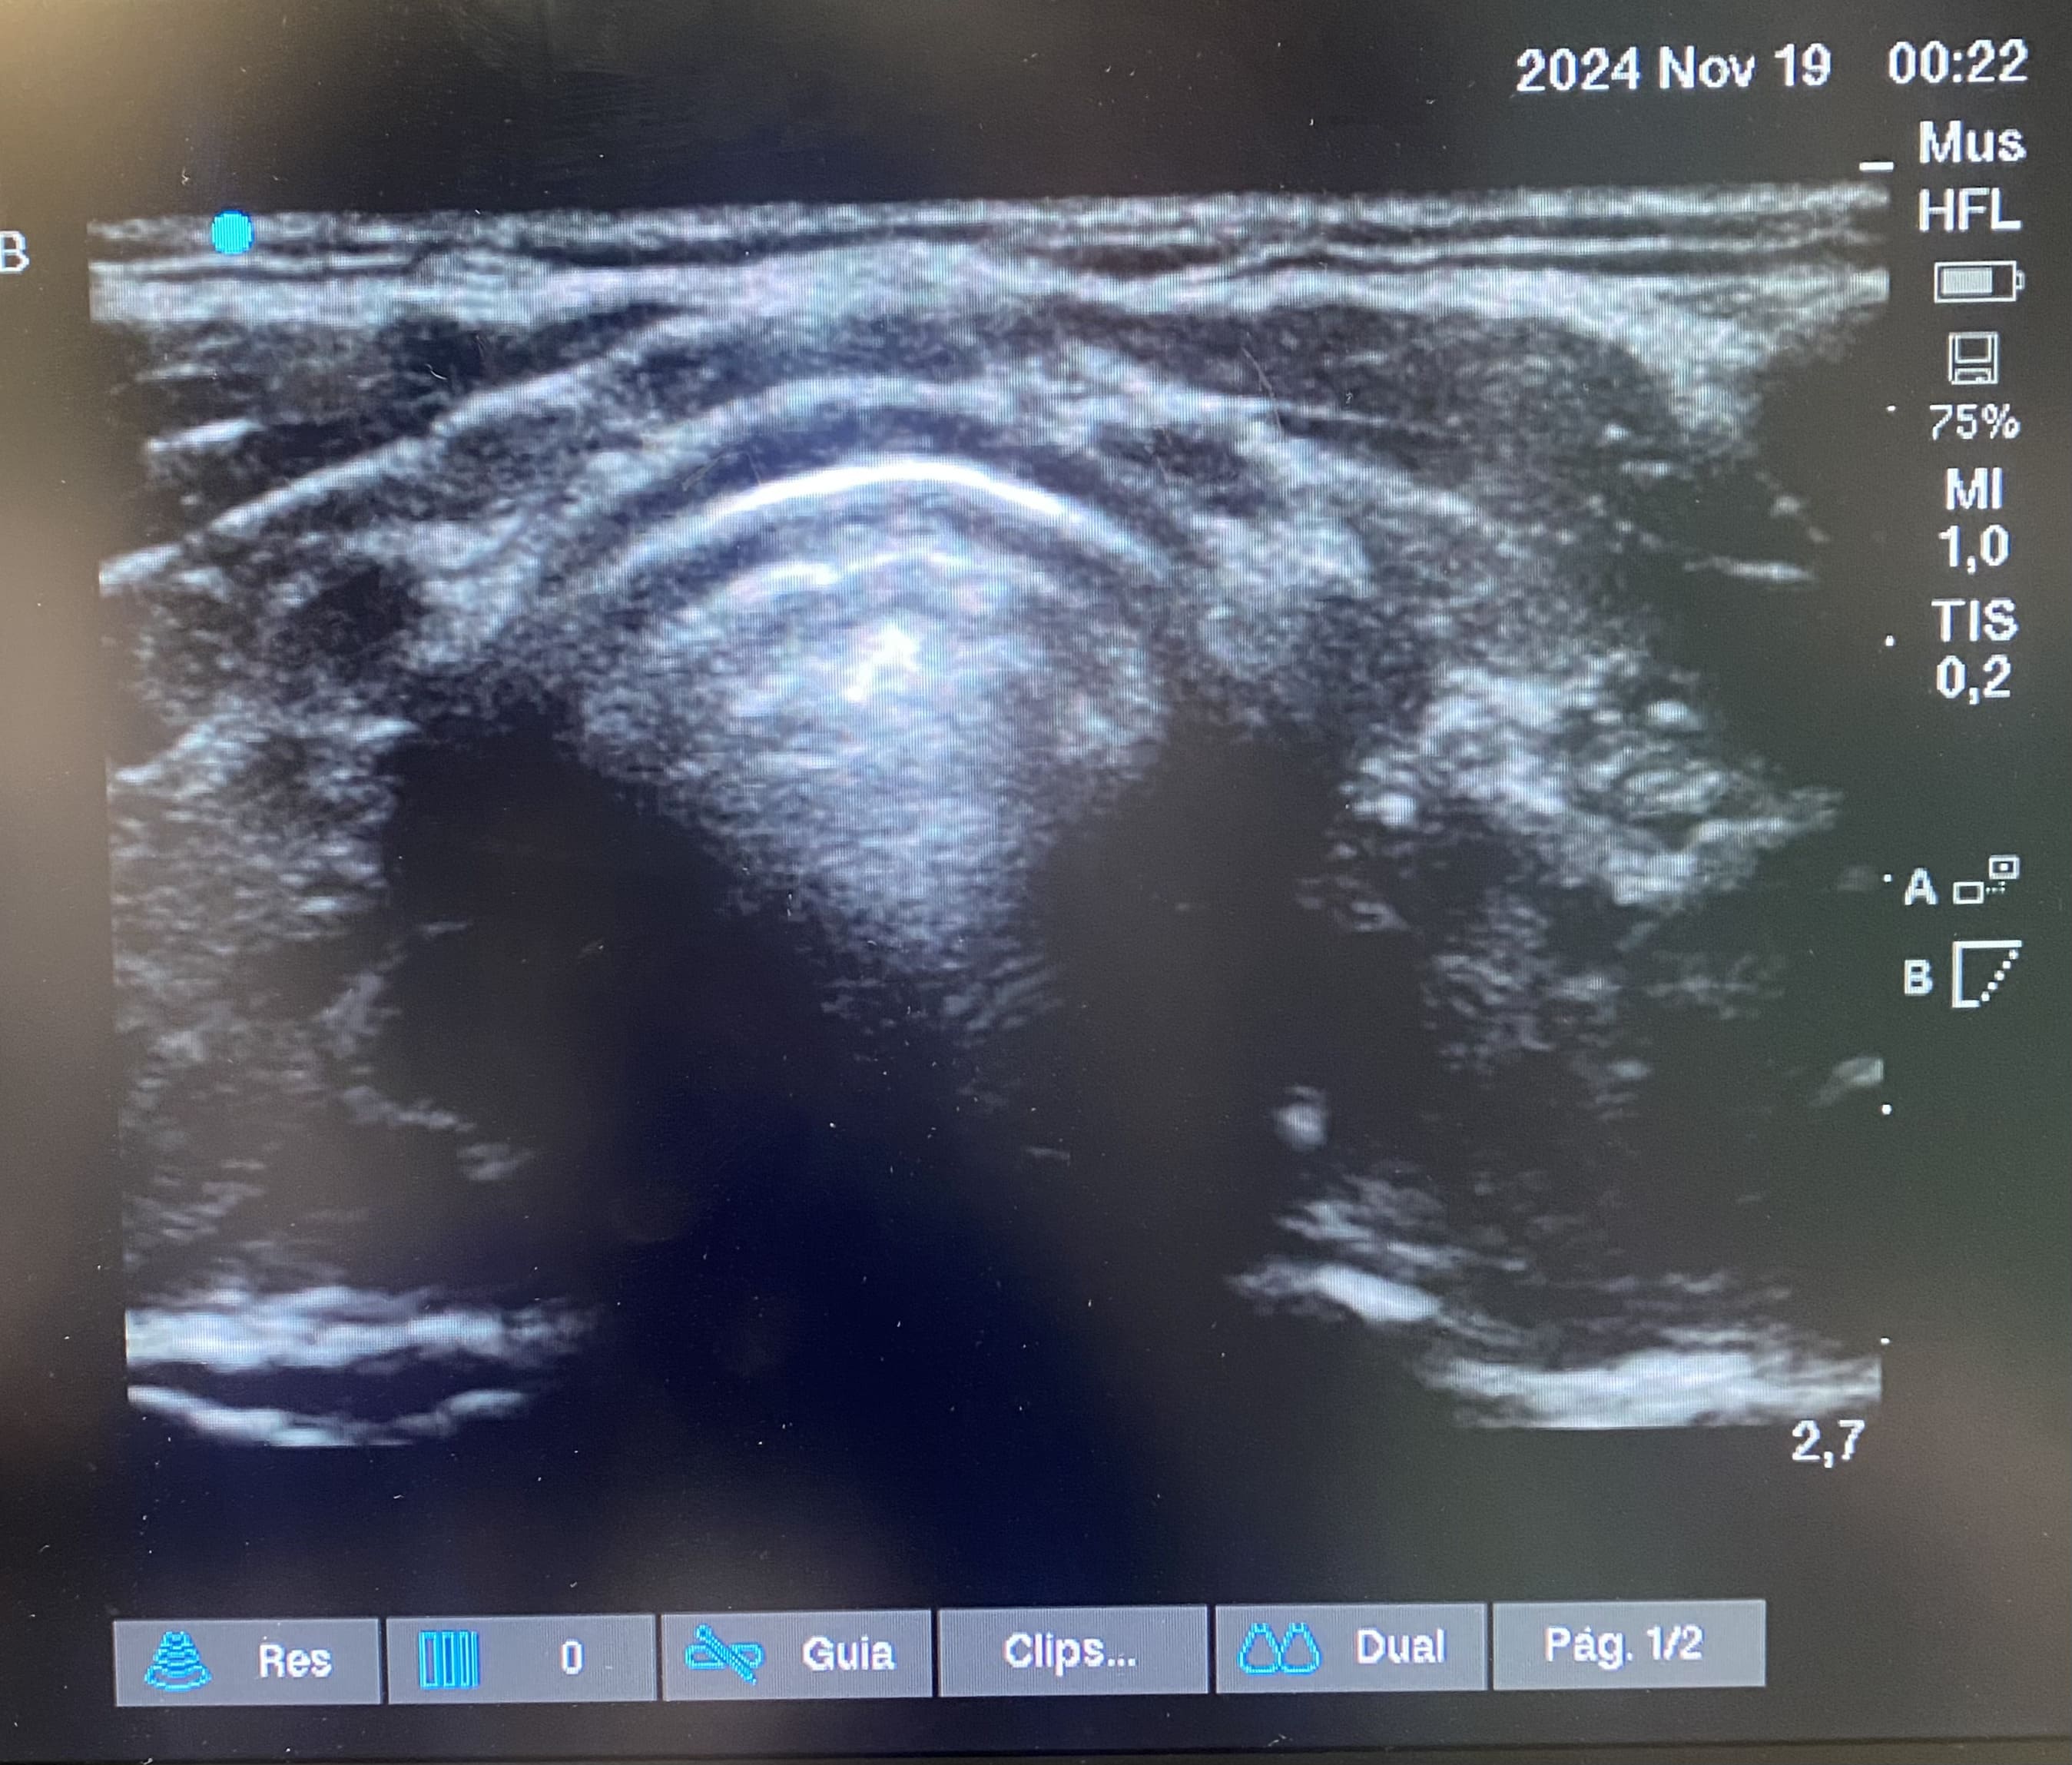

Planes de actuación: Se realiza ecografía en urgencias observándose glándulas tiroideas de tamaño normal con un patrón estructural alterado. Se inicia levotiroxina 50 mcg, se solicita ecografía reglada y anticuerpos (Ac) antitiroideos para control y seguimiento por su médico de atención primaria.

Ecografía de cuello-tiroides: Ambos lóbulos tiroideos presentan un tamaño dentro de la normalidad, con contorno lobulado, ecoestructura muy heterogénea con áreas seudonodulares y septos fibrosos y alguna pequeña formación quística. Hallazgos compatibles con tiroiditis probablemente autoinmune (valoración clínica y analítica).